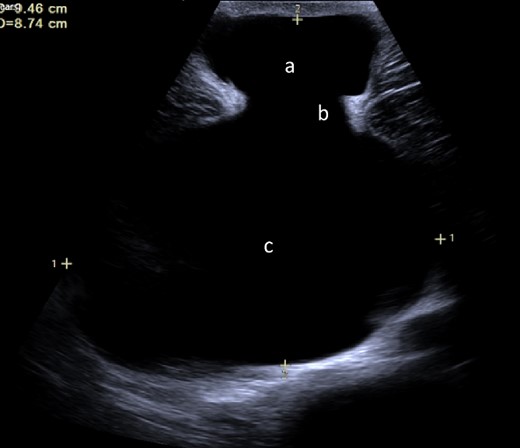

We present the case of a 26-year-old man who presented to the general surgery outpatient clinic with intermittent peri-umbilical pain, and the presence of a soft swelling palpable at his umbilicus. There was a positive cough impulse consistent with a true umbilical hernia and the patient described no previous medical or surgical history. An abdominal ultrasound scan visualized a large thin-walled serous fluid collection tracking into the peritoneal cavity (95 mm × 87 mm × 97 mm) (Fig. 1). Computed tomography (CT) of the abdomen and pelvis with contrast reported a large bi-lobed cystic mass centred at the right side of the mesentery, with herniation of part of the cyst along the umbilicus. Displacement of the small bowel with anterior extension into the abdominal wall was seen with the suggestion of posterior extension into the right retroperitoneal space (Figs 2 and 3). The patient underwent routine pre-operative work up and the cyst was excised through a midline para-umbilical laparotomy (Fig. 4) given the concern of retroperitoneal involvement. Intra-operatively, the hernia neck and the root of the cyst were found at the base of the umbilical cicatrix with no attachment to the mesentery. The cyst was loculated and filled with clear fluid. It was dissected off the peritoneal tissues and off from the posterior umbilical skin prior to removal. There was evidence of rupture of one of the locules and clear fluid was drained.

Ultrasound image demonstrating fluid collection within the umbilicus (a) tracking into abdominal cavity (c) originating from the cicatrix (b).